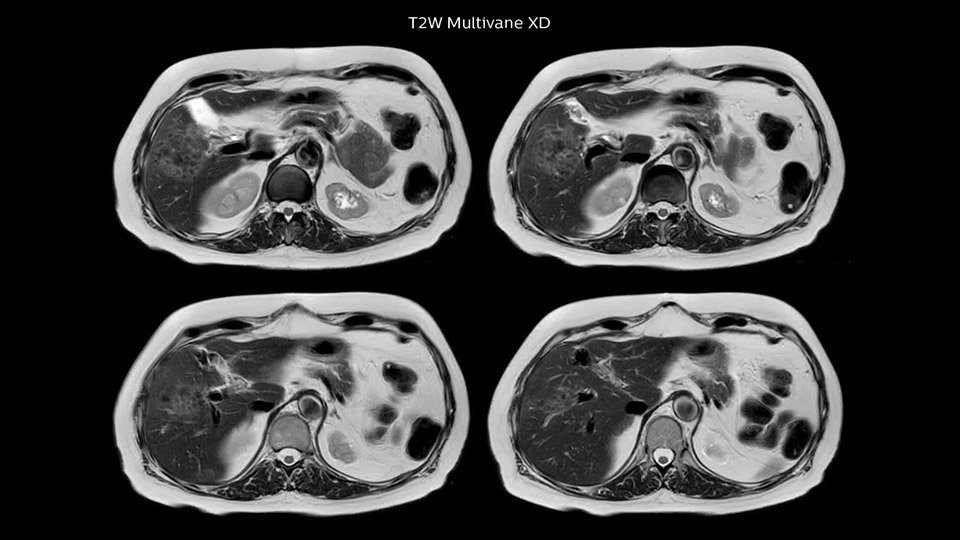

Dr. Baumann then implemented MultiVane XD for motion correction. It uses an extended reconstruction algorithm for imaging that is virtually motion free. “With MultiVane XD we get excellent motion-corrected images with high spatial resolution. We typically first optimize our scan for high image quality, and when satisfied with that, we try to reduce the scan time. So, we combined MultiVane XD with dS SENSE, which allows us to shorten the scan time,” he explains. “The performance of MultiVane XD in liver imaging is outstanding. MultiVane XD with dS SENSE is a powerful development in improving liver image quality.” “As we use breathhold imaging for T2-weighted liver scans, we depend on the patient’s ability to cooperate with the exam. This can present a real challenge when we are looking for small lesions, such as in our oncological patients. However, with MultiVane XD motion correction, we get excellent images. This is important for our surgeons, because they want to know exactly where the lesions are.”

“Our liver exams are quite fast,” says Dr. Baumann. “If the patient tolerates it, we use an arms-up position to reduce the FOV and speed up the exam with dS SENSE.” “We acquire one transversal high resolution T2-weighted sequence with 3 mm slice thickness, for example for pancreas or liver lesions. Then we also add a T2 fat suppressed MultiVane XD SPIR sequence. We perform these two routinely in our liver imaging. We use high dS SENSE factors to significantly shorten scan times to 2-4 minutes, which can improve our protocol; it’s a very robust scan.” “We include mDIXON for the dynamic sequences because of the robust and homogeneous fat suppression we get with that. We had been using eTHRIVE, but we are now quite happy with mDIXON. Sometimes we use a medication to calm the bowels, to further improve the image quality.”

“We are more confident in our diagnosis if we don’t have to rescan the patient and compare it to other studies; this liver exam gives us good image quality in a faster time than the default system’s approach with arms down. That makes a difference for the patients, too. The shorter scan times, especially with the high dS SENSE factors, shorten the duration of the total examination. At the same time it’s more comfortable for the patient, to rest normally without holding the breath, just relaxing.”